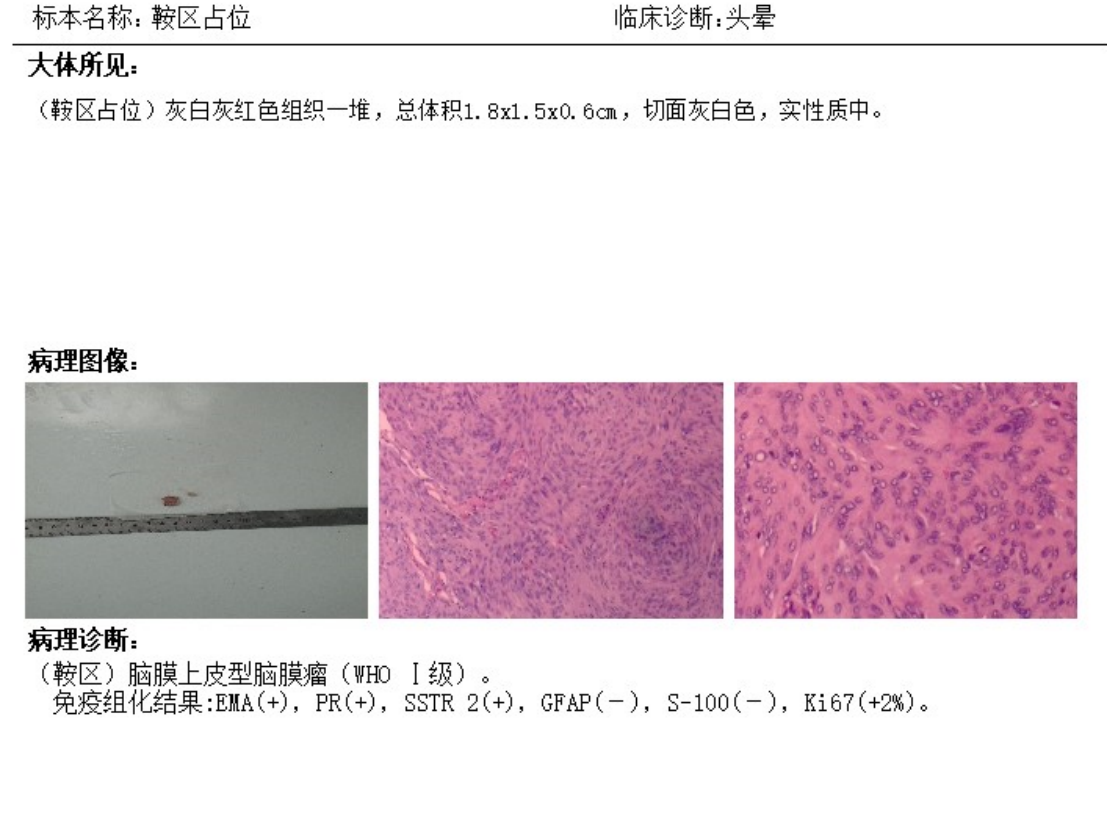

术后CT